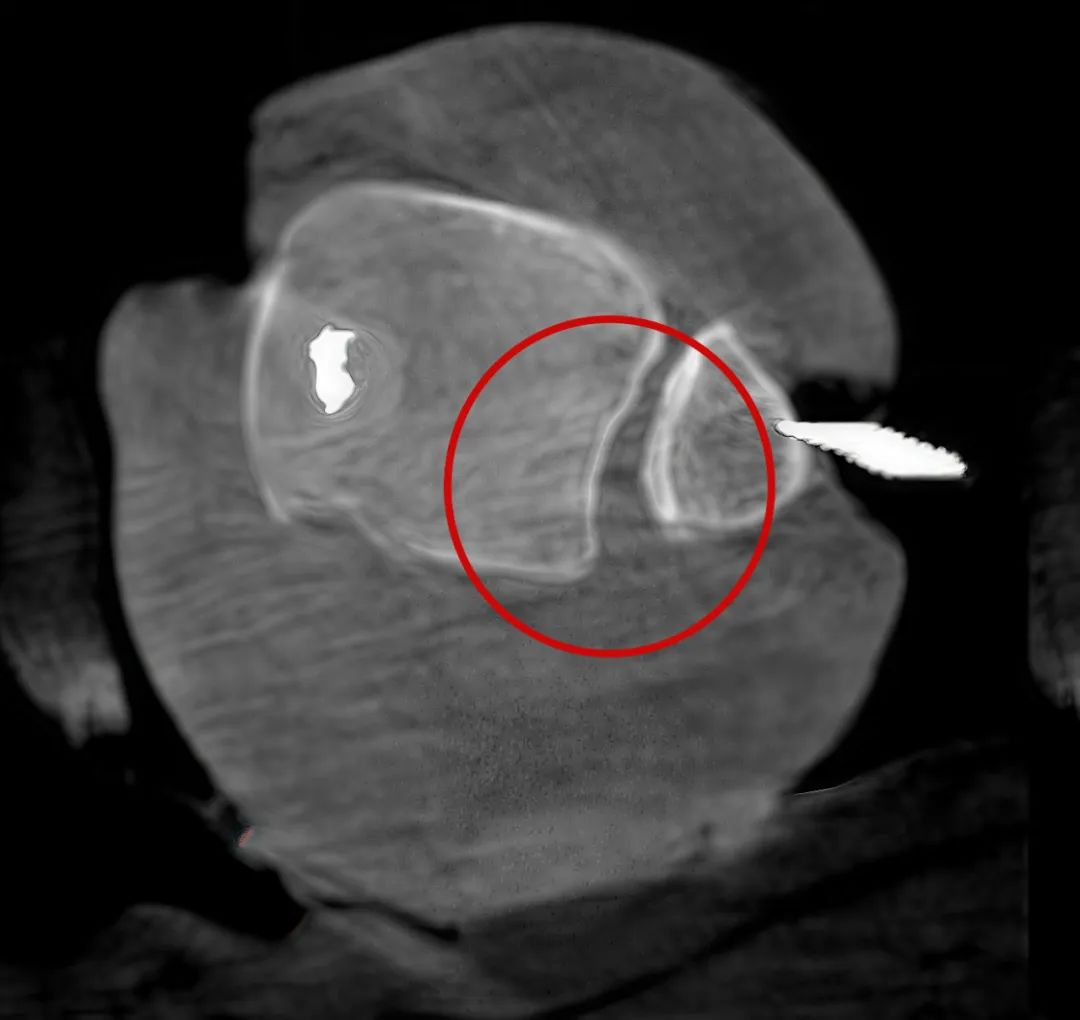

從三維影像看,復位欠佳,貼合度不夠

二維C形臂提供的影像存在固有局限性,其成像原理是基于單一方位的投影,導致深部解剖結構信息缺失,且容易受到骨骼和組織的重疊干擾,使得部分病灶難以清晰顯示,甚至被掩蓋。相比之下,三維C形臂通過三維重建技術,可以獲得類似CT的斷層掃描圖像,從而解決了二維影像的重疊問題。

醫生能夠利用這些三維圖像,更直觀、更深入地分析病變,進行全方位觀察,例如:精確評估骨折復位情況、清晰顯示內植入物的位置及其與周圍組織的關系等。尤其在復雜骨折、脊柱手術、呼吸介入等臨床場景中,三維C形臂提供的詳細信息對手術導航和療效評估至關重要。